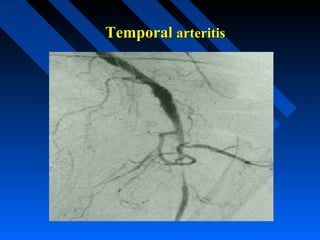

Giant Cell Arteritis

(Temporal arteritis)

• Occurring primarily over the age of 50

years.

• Frequent features include fatigue,

temporal headaches, jaw claudication,

loss of vision, scalp tenderness,

polymyalgia rheumatica and aortic arch

syndrome.

• Rarely involves the skin, kidneys and

lungs.

Temporal arteritis